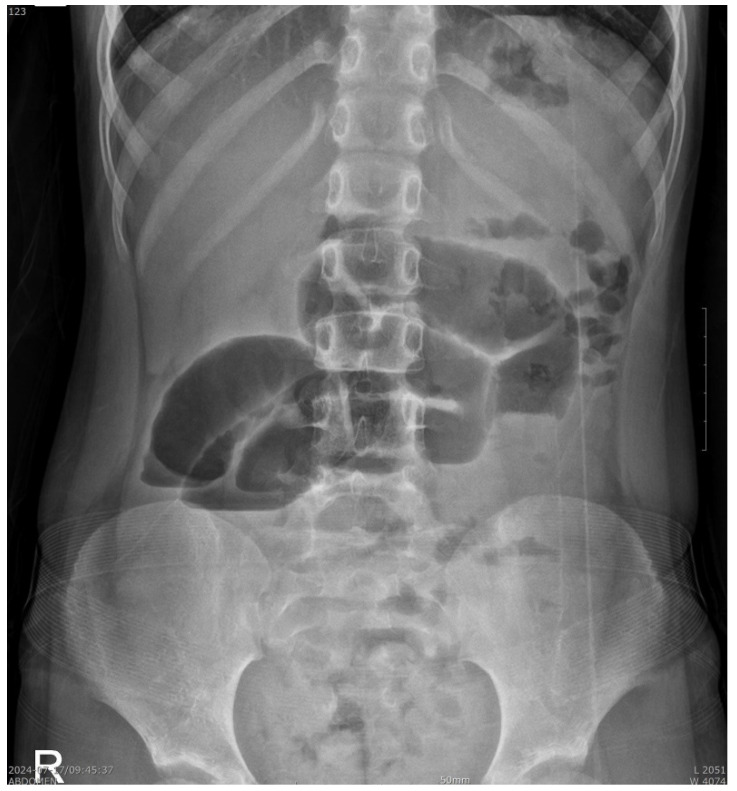

Case presentation: We report the case of a 6-year-old girl who presented to our pediatric emergency center with complaints of acute abdominal pain, vomiting, and diarrhea. She had no notable medical history, including perinatal, surgical, or psychiatric disorders. After finding a bezoar-like structure through a combined enteritis CT scan, reassessing the child's dietary concerns revealed that the child had experienced symptoms of trichophagia for approximately 3 to 4 years. Enterotomy and the removal of the bezoar were successfully performed. A pediatric psychiatric consultation was carried out to prevent further trichophagia-induced complications.